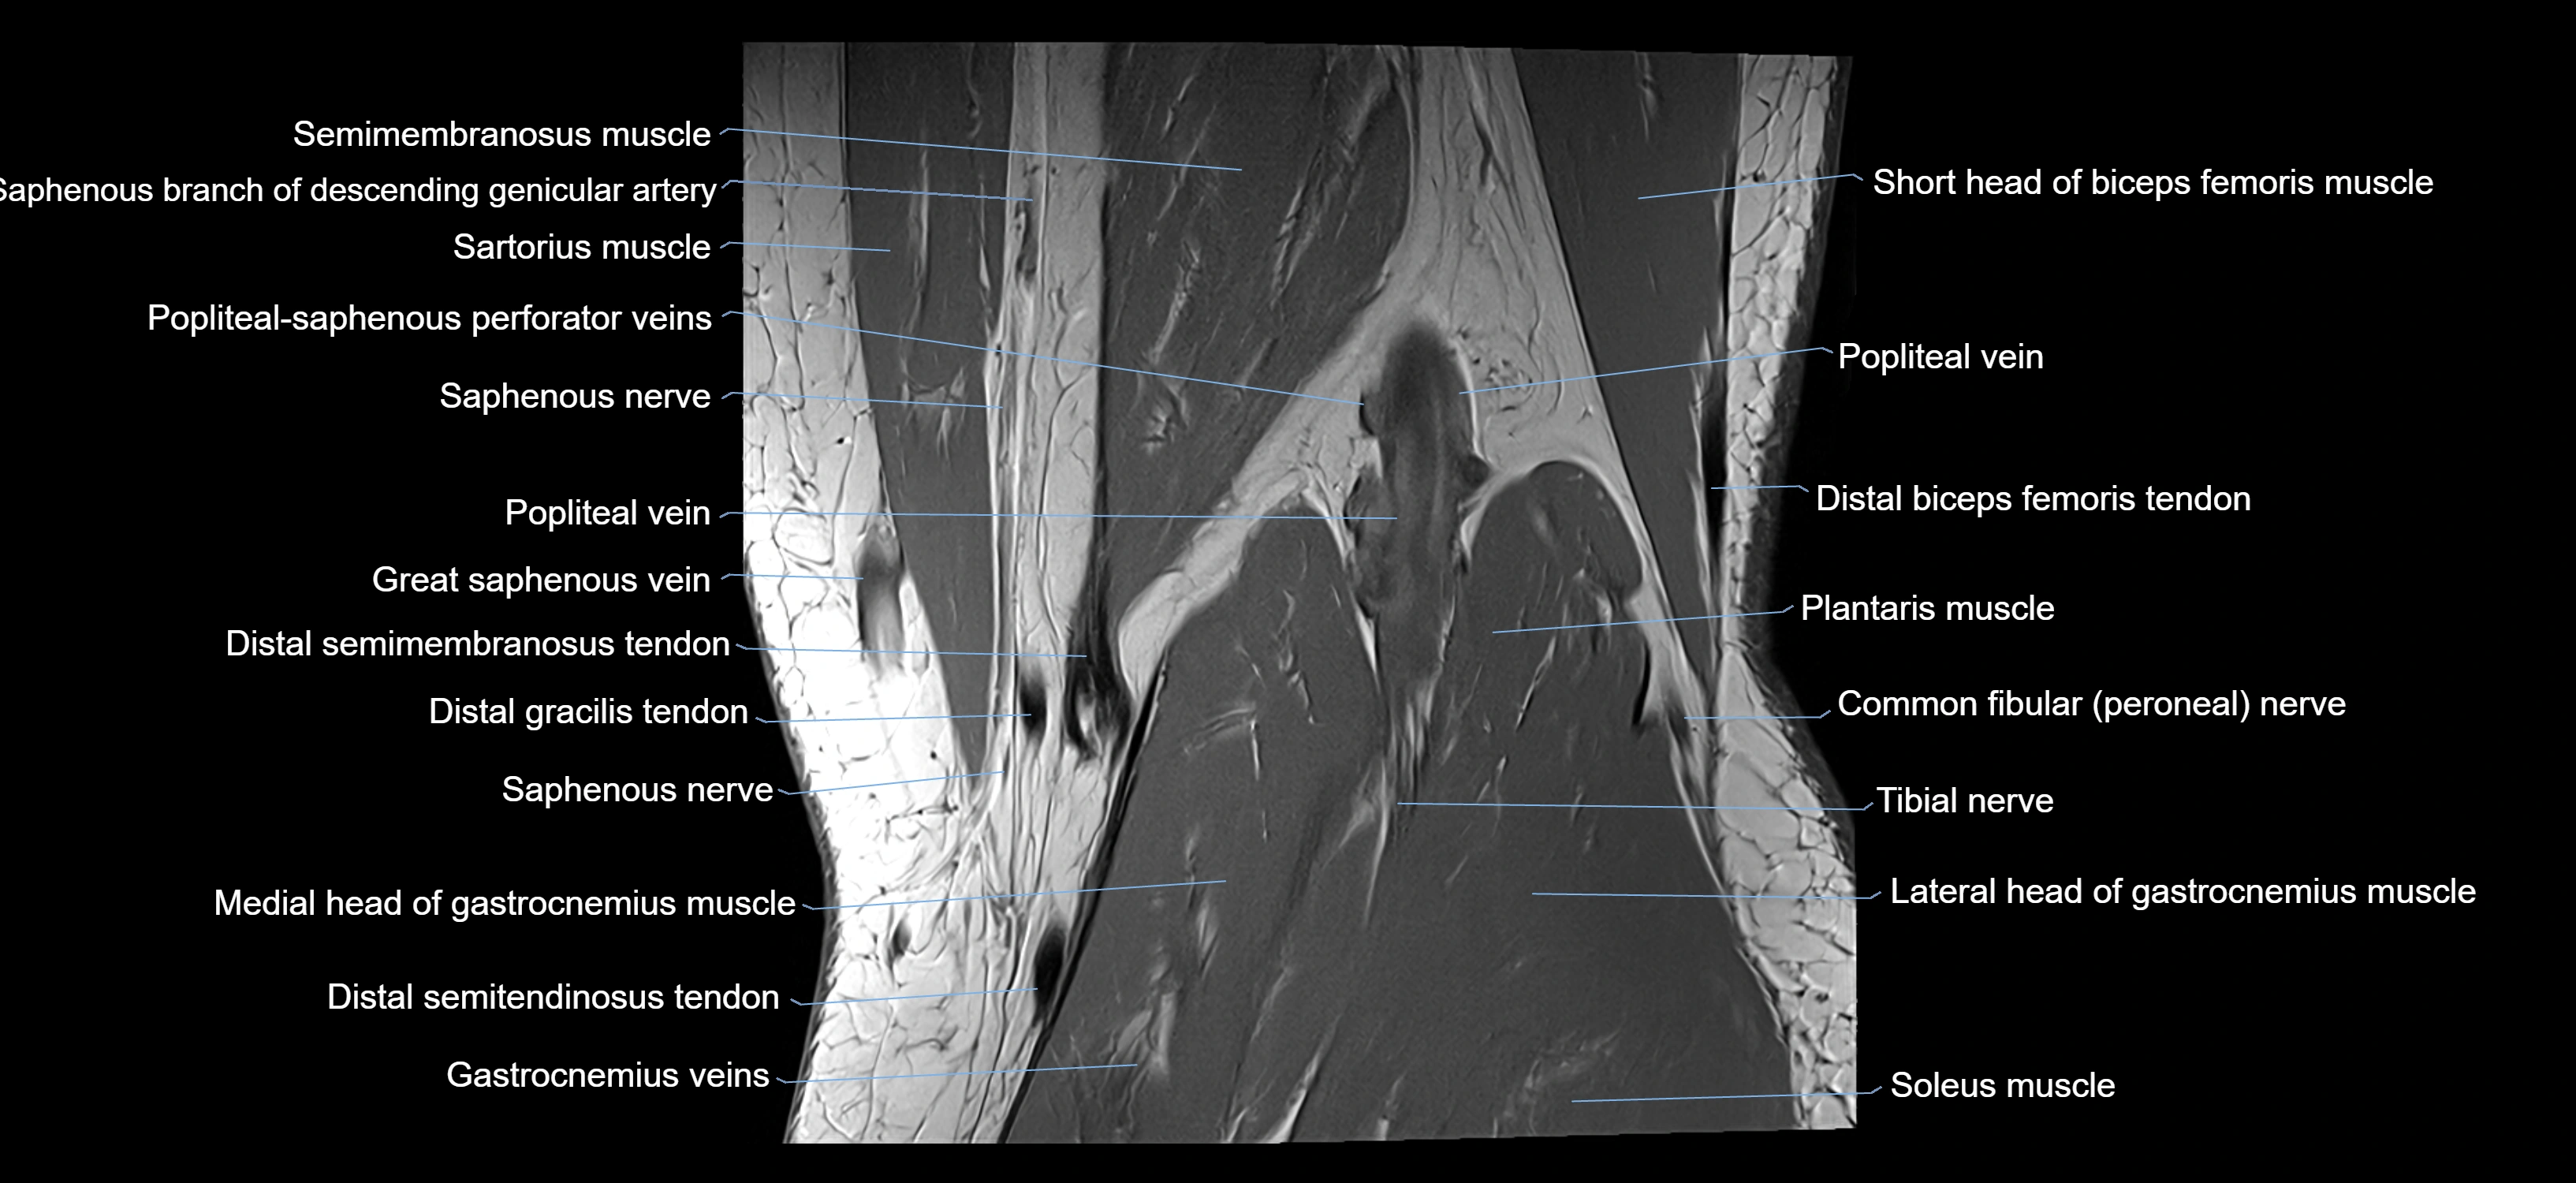

- Distal semimembranosus tendon

- Distal semitendinosus tendon

- Gracilis tendon (Distal)

- Lateral head of gastrocnemius muscle

- Medial head of gastrocnemius muscle

- Popliteal vein

- Popliteal–Saphenous perforating veins

- Saphenous nerve

- Sartorius muscle

- Semimembranosus muscle

- Semitendinosus muscle

- Soleus muscle

- Tibial nerve